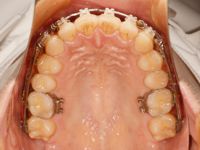

まずは調整前のお口の中の状態です![]()

かなり綺麗に並んでいますね![]()